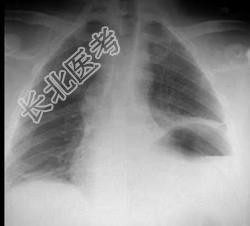

- 单项选择题35岁,男, 因车祸入院,呼吸困难、发绀、上腹痛, 请结合胸片和CT选择最可能的诊断 ( )

A、膈疝

B、胸腔积液

C、膈膨升

D、膈麻痹

E、液气胸